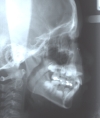

埋伏歯を矯正歯科的に牽引することで、正常咬合を確立できた症例。

埋伏歯は、歯の萌出する隙間の不足、萌出方向の不良、萌出力不足、腫瘍または囊胞などの障害物により萌出路が塞がれている場合などに生じる病気である。いったん萌出が妨げられると、原因が除去されても自然萌出に至らないことが多く、そのままでは埋伏歯が使えないだけでなく、正常咬合が確立できない事態となる。

最良の解決策は、口腔外科的に開窓後、矯正歯科的に牽引し咬合に参加させることである。単に萌出させたと言うだけでなく、牽引後マルチブラケット装置を使用し、正常咬合を確立したケースの提示が求められている。